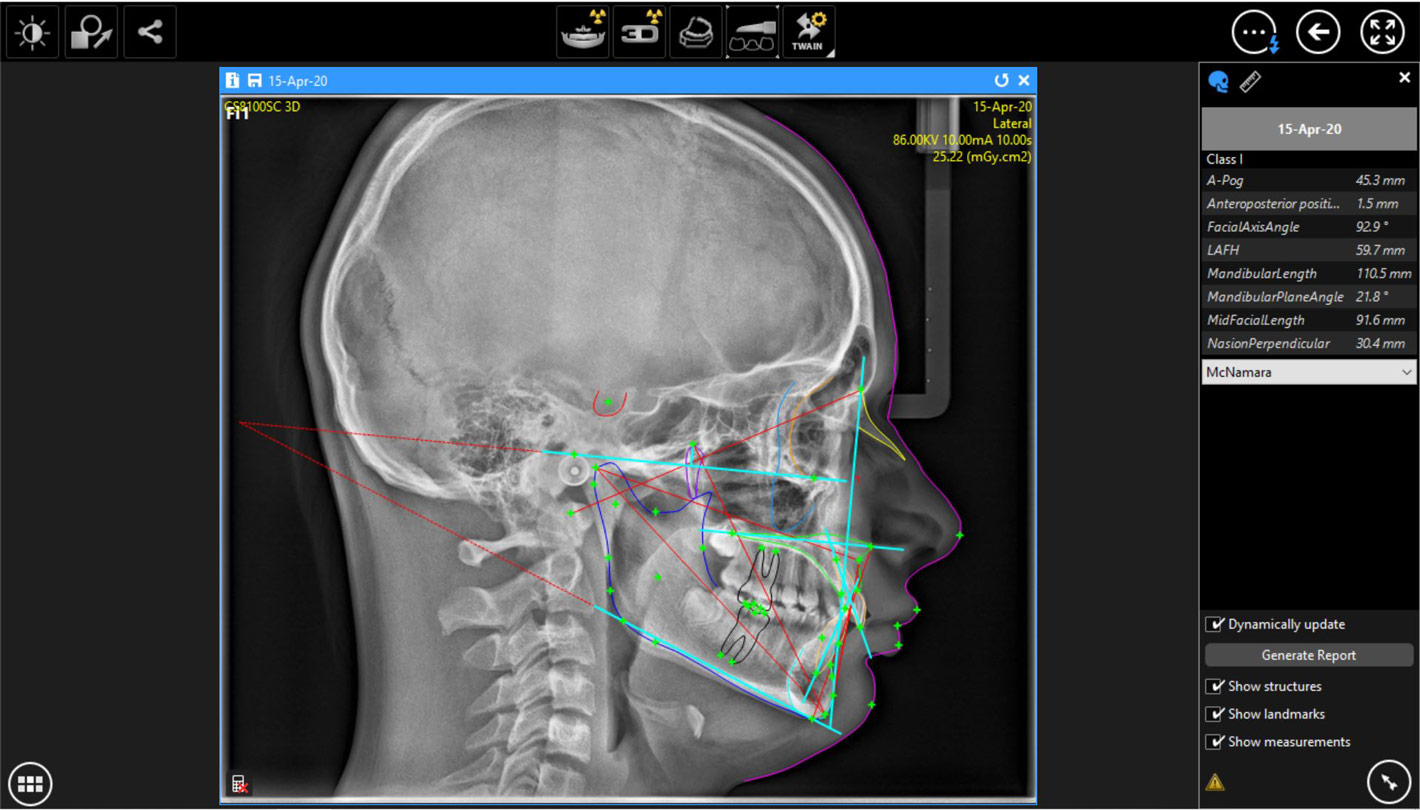

- Άριστη ψηφιακή Κεφαλομετρική ακτινογραφία (2D). (προαιρετικό)